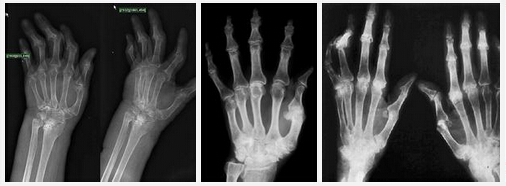

(圖:風(fēng)濕性關(guān)節(jié)炎的治療及預(yù)防方法不對極易致病情不斷惡化)

對于風(fēng)濕性關(guān)節(jié)炎,朋友們還需要注意飲食有節(jié)、起居有常,這是強(qiáng)身保健的主要措施。一旦患上風(fēng)濕性關(guān)節(jié)炎不及時治療會造成很嚴(yán)重的后果,并且引起很多并發(fā)癥,后來會導(dǎo)致關(guān)節(jié)畸形病變。